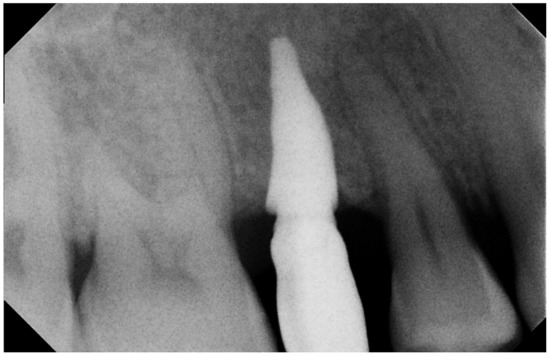

3. Results